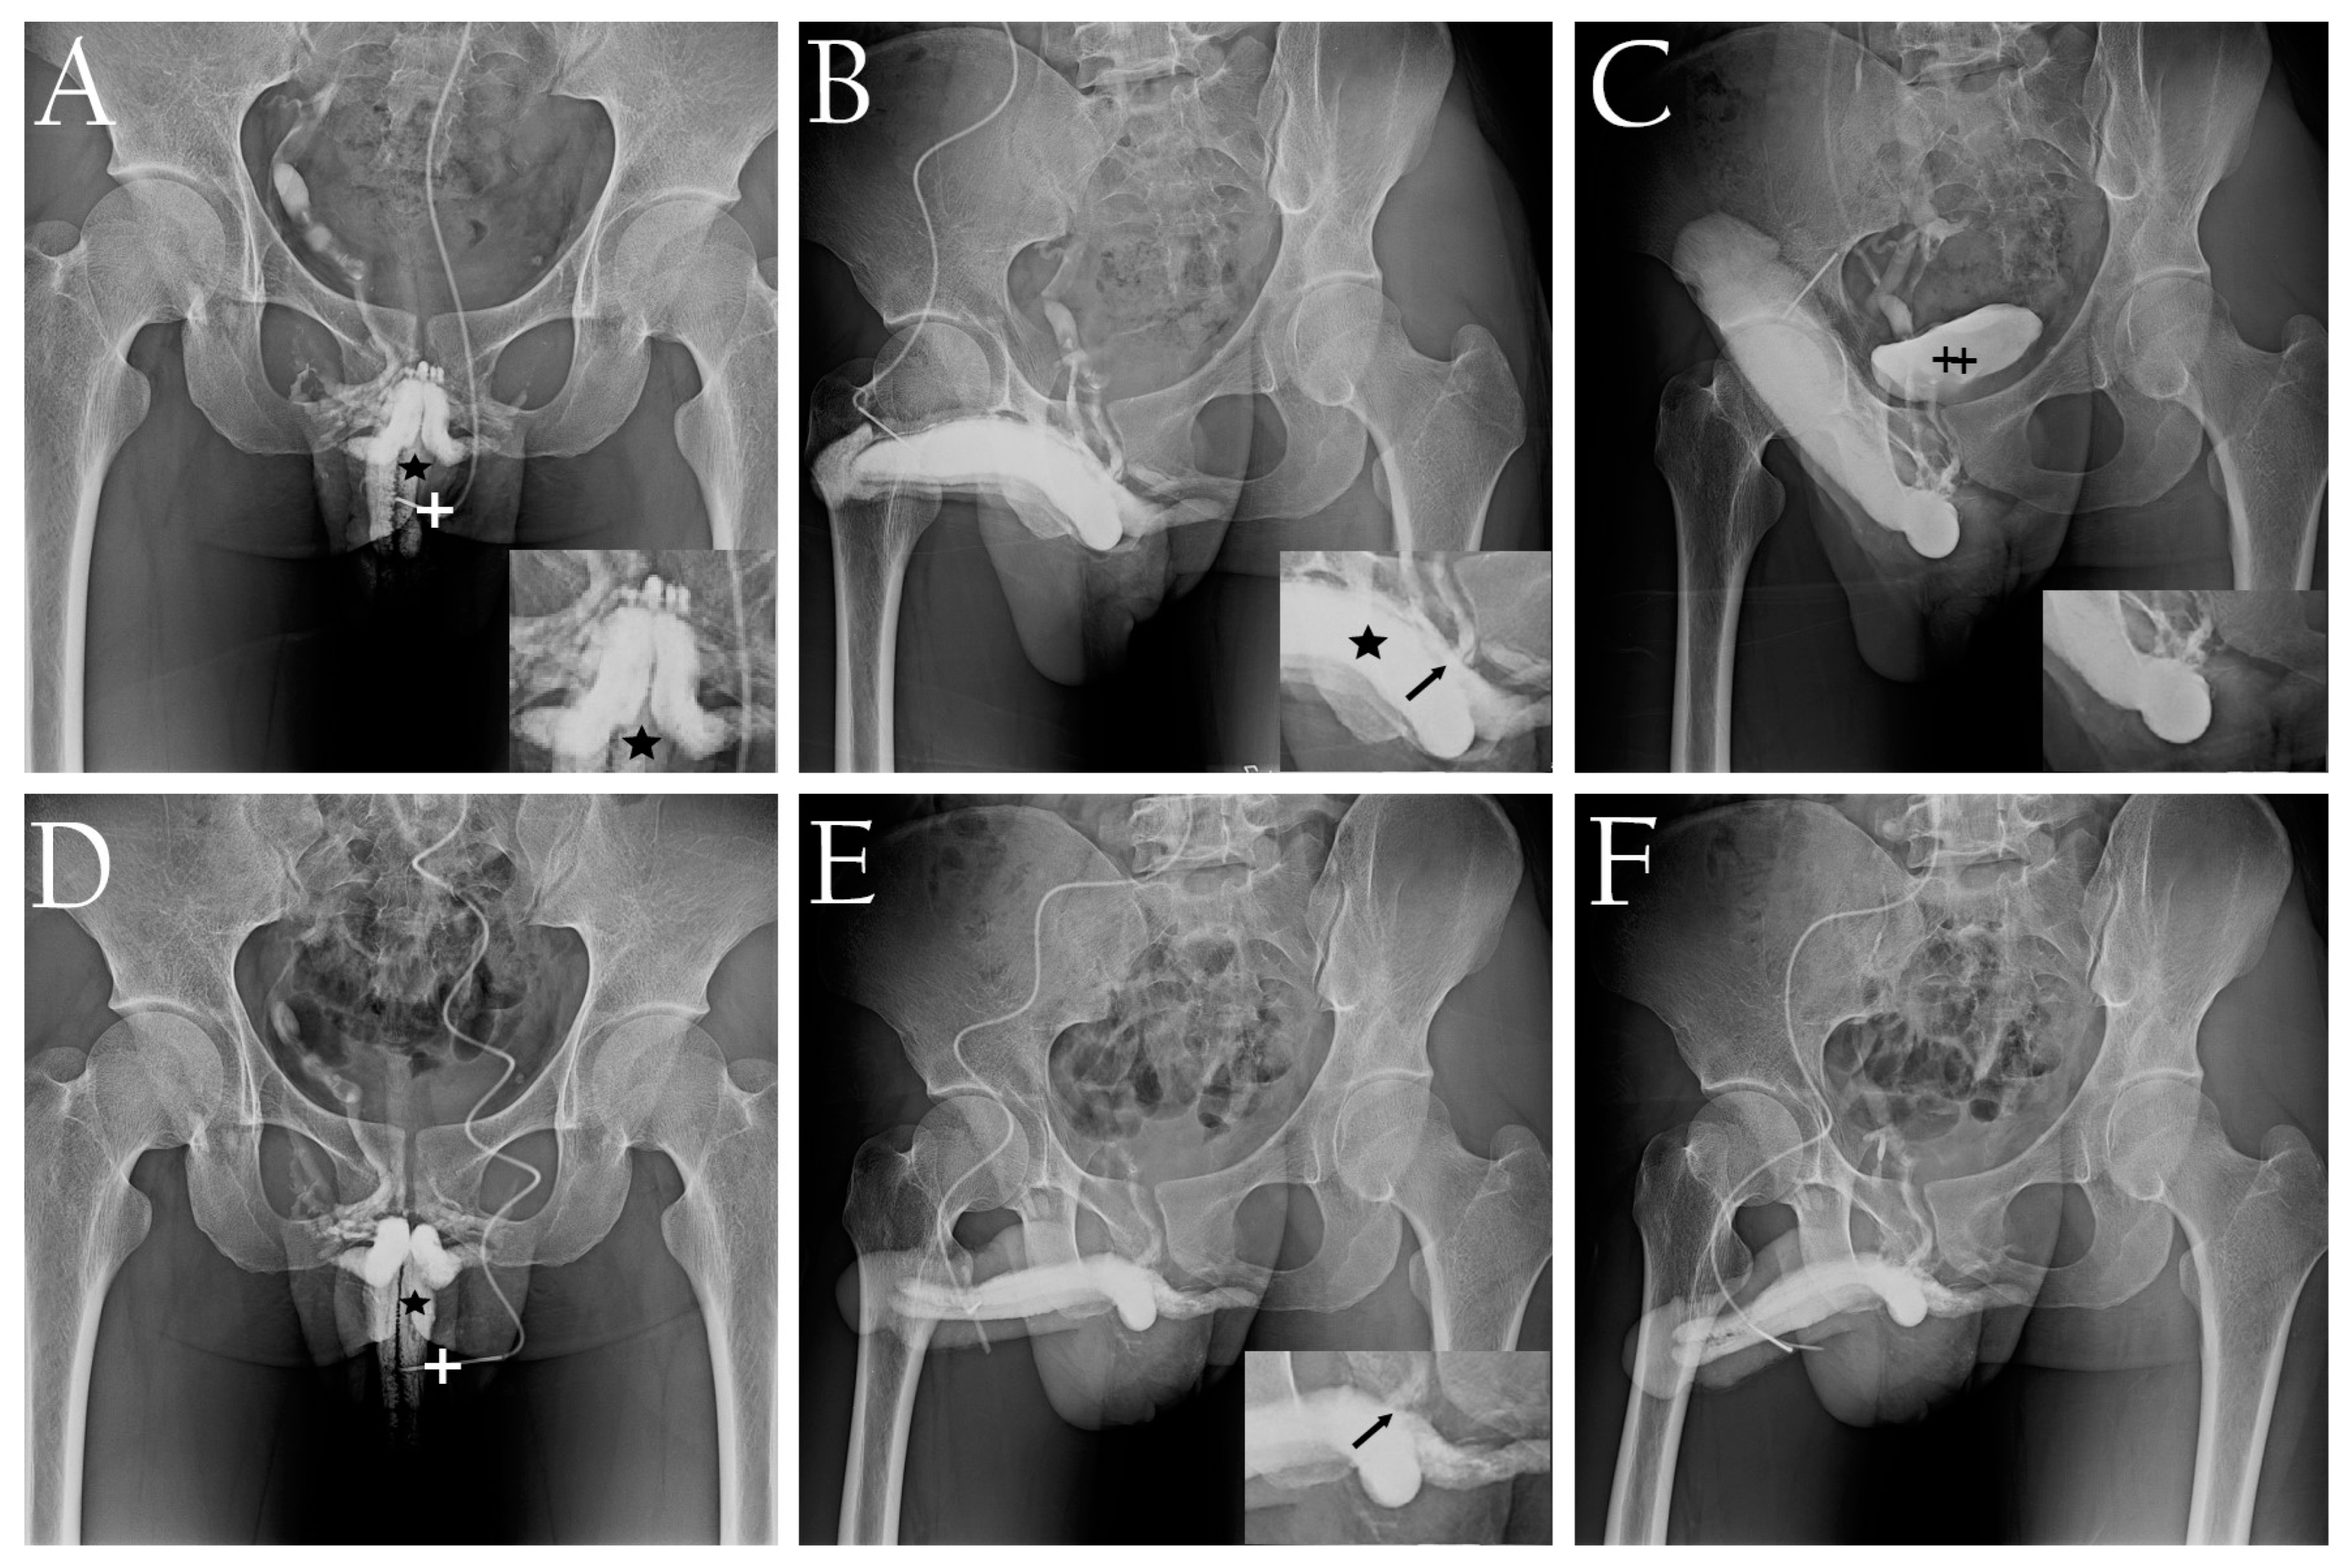

- Hsu, G.L.; Hill, J.W.; Chen, H.S.; Huang, S.J. Novel pilot films providing a dispensable information in pharmaco-cavernosography. Transl. Androl. Urol. 2014, 4, 398–405. [Google Scholar]